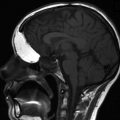

After the roof of the sphenoid and planum are identified (see above), posterior and anterior ethmoidectomy is performed in a posterior-to-anterior direction with the use of 0° and 30° endoscopes. The lowest part of the anterior skull base is the cribriform plate, which is located in the midline between the sphenoid and frontal sinuses (Fig. 10.19). In the pediatric patient, the cribriform is flat and the sinuses are missing (Fig. 10.20).